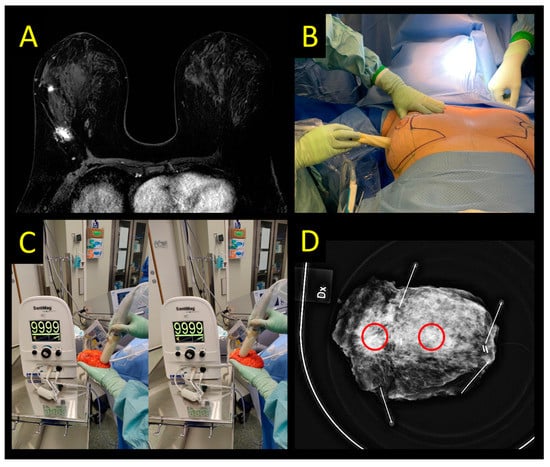

2.3. Magnetic and Paramagnetic Localization

2.4. Sirius Pintuition

2.5. Radar Reflector Localization